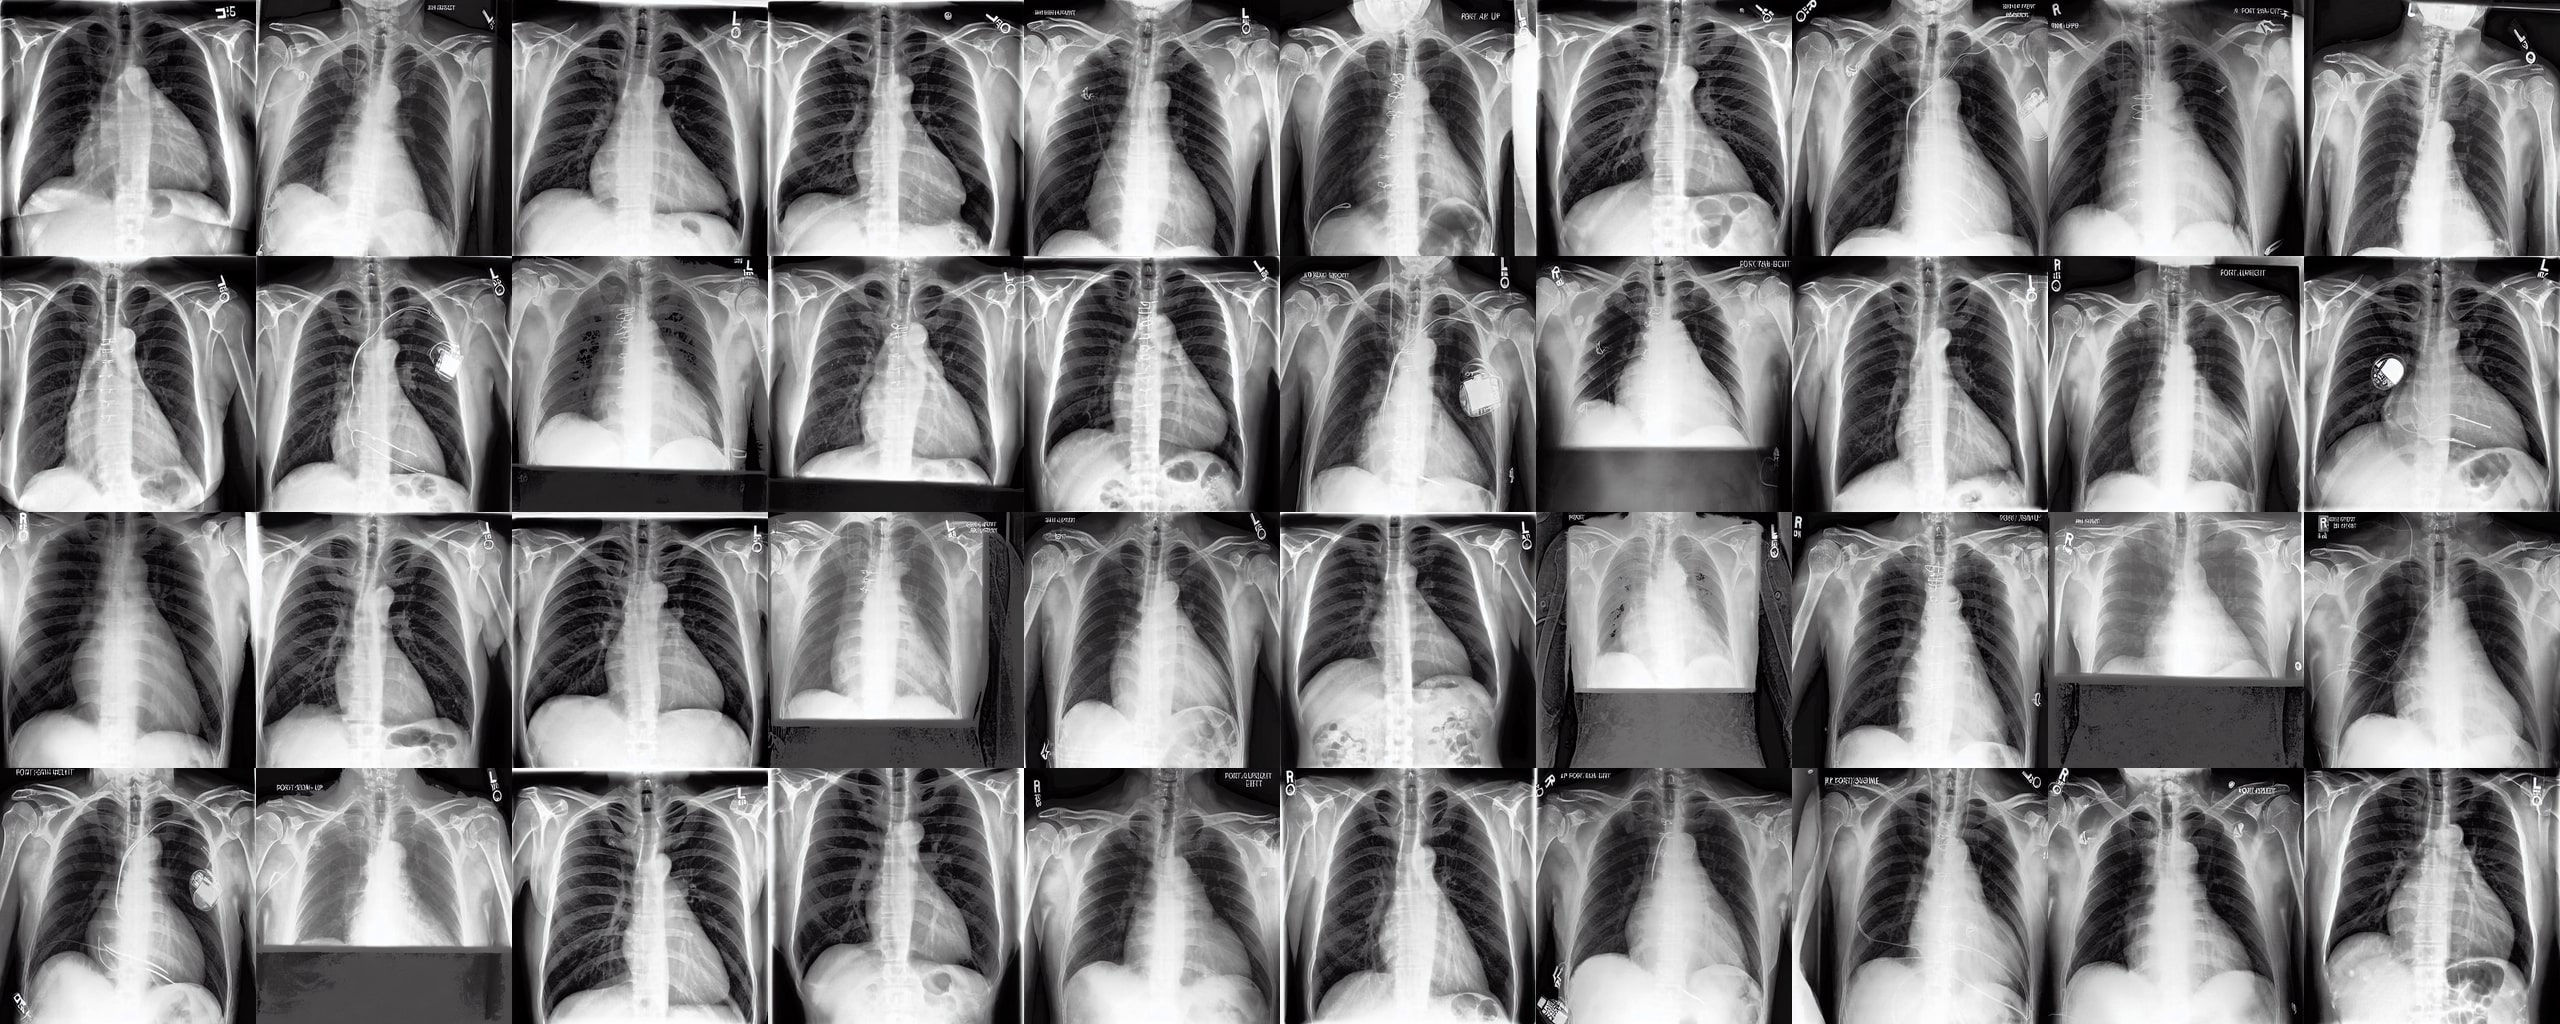

Chest X-rays We use the CheXpert dataset 10.1609/aaai.v33i01.3301590, which contains 170k training images. This dataset contains diversity in medical devices (such as chest tubes and wires), diseases (such as pneumonia and pleural-effusion) and anatomical details. We implement Rainbow on top of frozen parameters of a finetuned Stable Diffusion v1.5 (SD1.5) by previous work kumar2025prism for chest X-ray data. We generate 2D chest X-ray images based on text prompt conditions, e.g., "Chest X-ray showing Support Devices". In addition to the finetuned SD1.5, we include RadEdit perez2024radedit, a model trained from scratch on multiple chest radiology data such as CheXpert irvin2019chexpert, MIMIC-CXR johnson2019mimic, and NIH-CXR wang2017chestxray data for image editing tasks (more details at Appendix D.3), in the result comparison. Rainbow’s graph generator module includes , , and .

Chest X-rays Figure 4b quantifies generations by Rainbow and baselines using FID and VS. Rainbow achieves a higher VS, indicating greater diversity than the finetuned SD model, while also improving image quality with a lower FID score. Both Rainbow and SD outperform the RadEdit. Figure 6 provides a qualitative comparison, images are generated using the prompt "Chest X-ray showing support devices", where Rainbow generates a more diverse set of medical devices, such as pacemakers, in all generations, while baselines do not show any devices in some images. All models achieve similar CLIP scores of . Additional results including generations, Figure 22 and numeric results, Table 4, are outlined in Appendix E.

We apply the same approach to chest X-rays to explore the set of "support devices" edges by extracting the 10 most frequently added edges when changing the prompt from "Chest X-ray with no significant finding" to "Chest X-ray showing support devices" (visualized in Figure 25 in Appendix E). Figure 8 shows the transformation with added "support devices" edges into trajectories with the appearance of medical devices in the generated images.